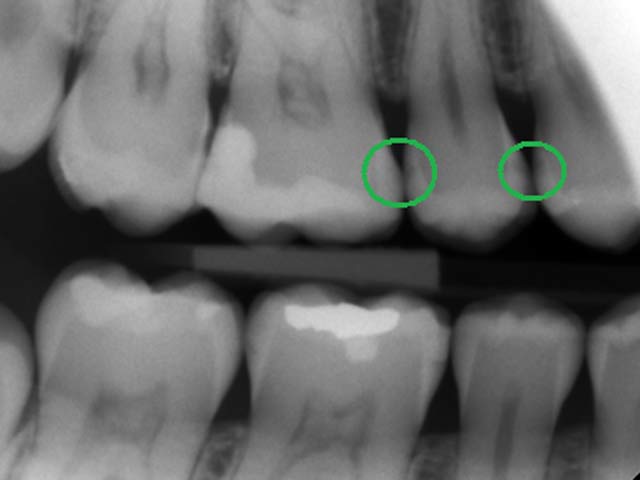

Дентальные снимки и диагностика кариеса